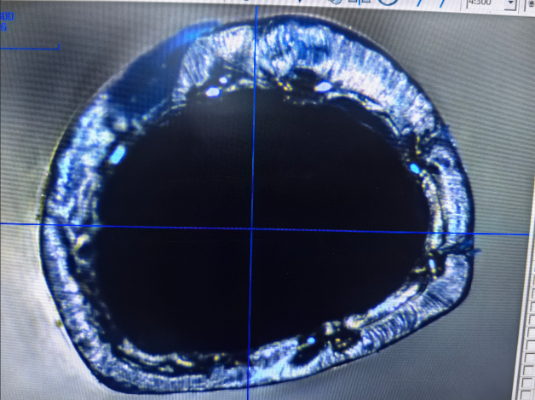

القسطرة المضفرة هي قسطرة طبية مصممة بهيكل مضفر وشكل مقطعي محدد. يتم استخدامه عادةً في الإجراءات الطبية التي تتطلب معدلات تدفق عالية وثباتًا. الميزة البارزة لهذه القسطرة هي الجمع بين جدرانها الداخلية والخارجية مع مواد مضفرة، مما يعزز نقل السوائل مع الحفاظ على المرونة والمتانة.

يشير الجانب "المحدد" لهذه القسطرة إلى حقيقة أن مقطعها العرضي ليس دائرة بسيطة، ولكنه شكل مصمم خصيصًا، مثل القطع الناقص أو المضلع أو الأشكال الأخرى غير الدائرية. تضيف الطبقة المضفرة القوة، مما يمكّن القسطرة المضفرة من تحمل الضغوط الداخلية والخارجية، والحفاظ على شكلها ووظيفتها حتى تحت الضغط.